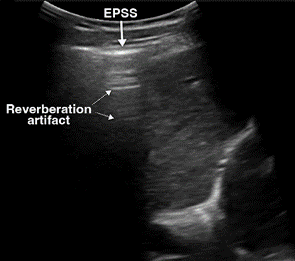

On US, free air is evaluated by focusing on the least dependent areas in the peritoneal cavity, where the air tends to migrate. In a supine patient, air moves anteriorly toward the interface between the peritoneal cavity and anterior abdominal wall and is often best identified in the RUQ over the liver [9, 49]. The highly reflective surface of air produces increased echogenicity of the peritoneal line, which is referred to as the enhanced peritoneal stripe sign. Often accompanying this is reverberation artifact, consisting of repeating hyperechoic horizontal lines directly below the enhanced peritoneal line. “Dirty” shadowing may be seen, obscuring the underlying organs (Fig. 8A). Because air can move freely within the peritoneal cavity, these findings change with patient position, known as shifting phenomenon [9, 47, 49]. Similarly, the scissors maneuver can help detect free air and visualize its movement. This technique consists of applying pressure with the probe over the liver to displace the free air and associated artifacts, making these findings less prominent. When the compression is released, the free air returns and associated artifacts become visible again [50].

An important potential pitfall is mistaking free air for intraluminal bowel gas. To differentiate between the two, it helps to focus on the hepatic region where bowel gas is minimal and consider position change or compression to help further identify pneumoperitoneum. Free air moves independent of respiration and peristalsis, unlike intraluminal air in the bowel [9, 47].